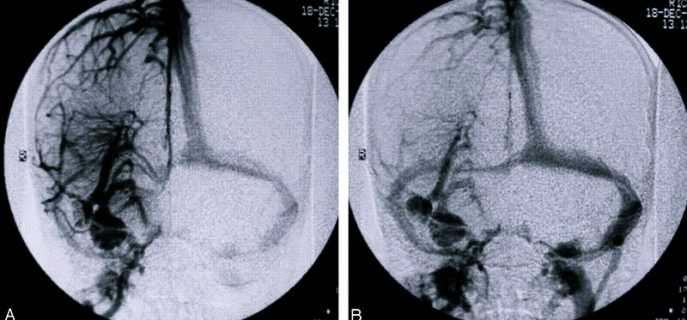

- Ангиография. Проводится на рентгенологическом оборудовании с применением контрастного вещества. Для ввода препарата в сосуды больному требуется легкая анестезия.